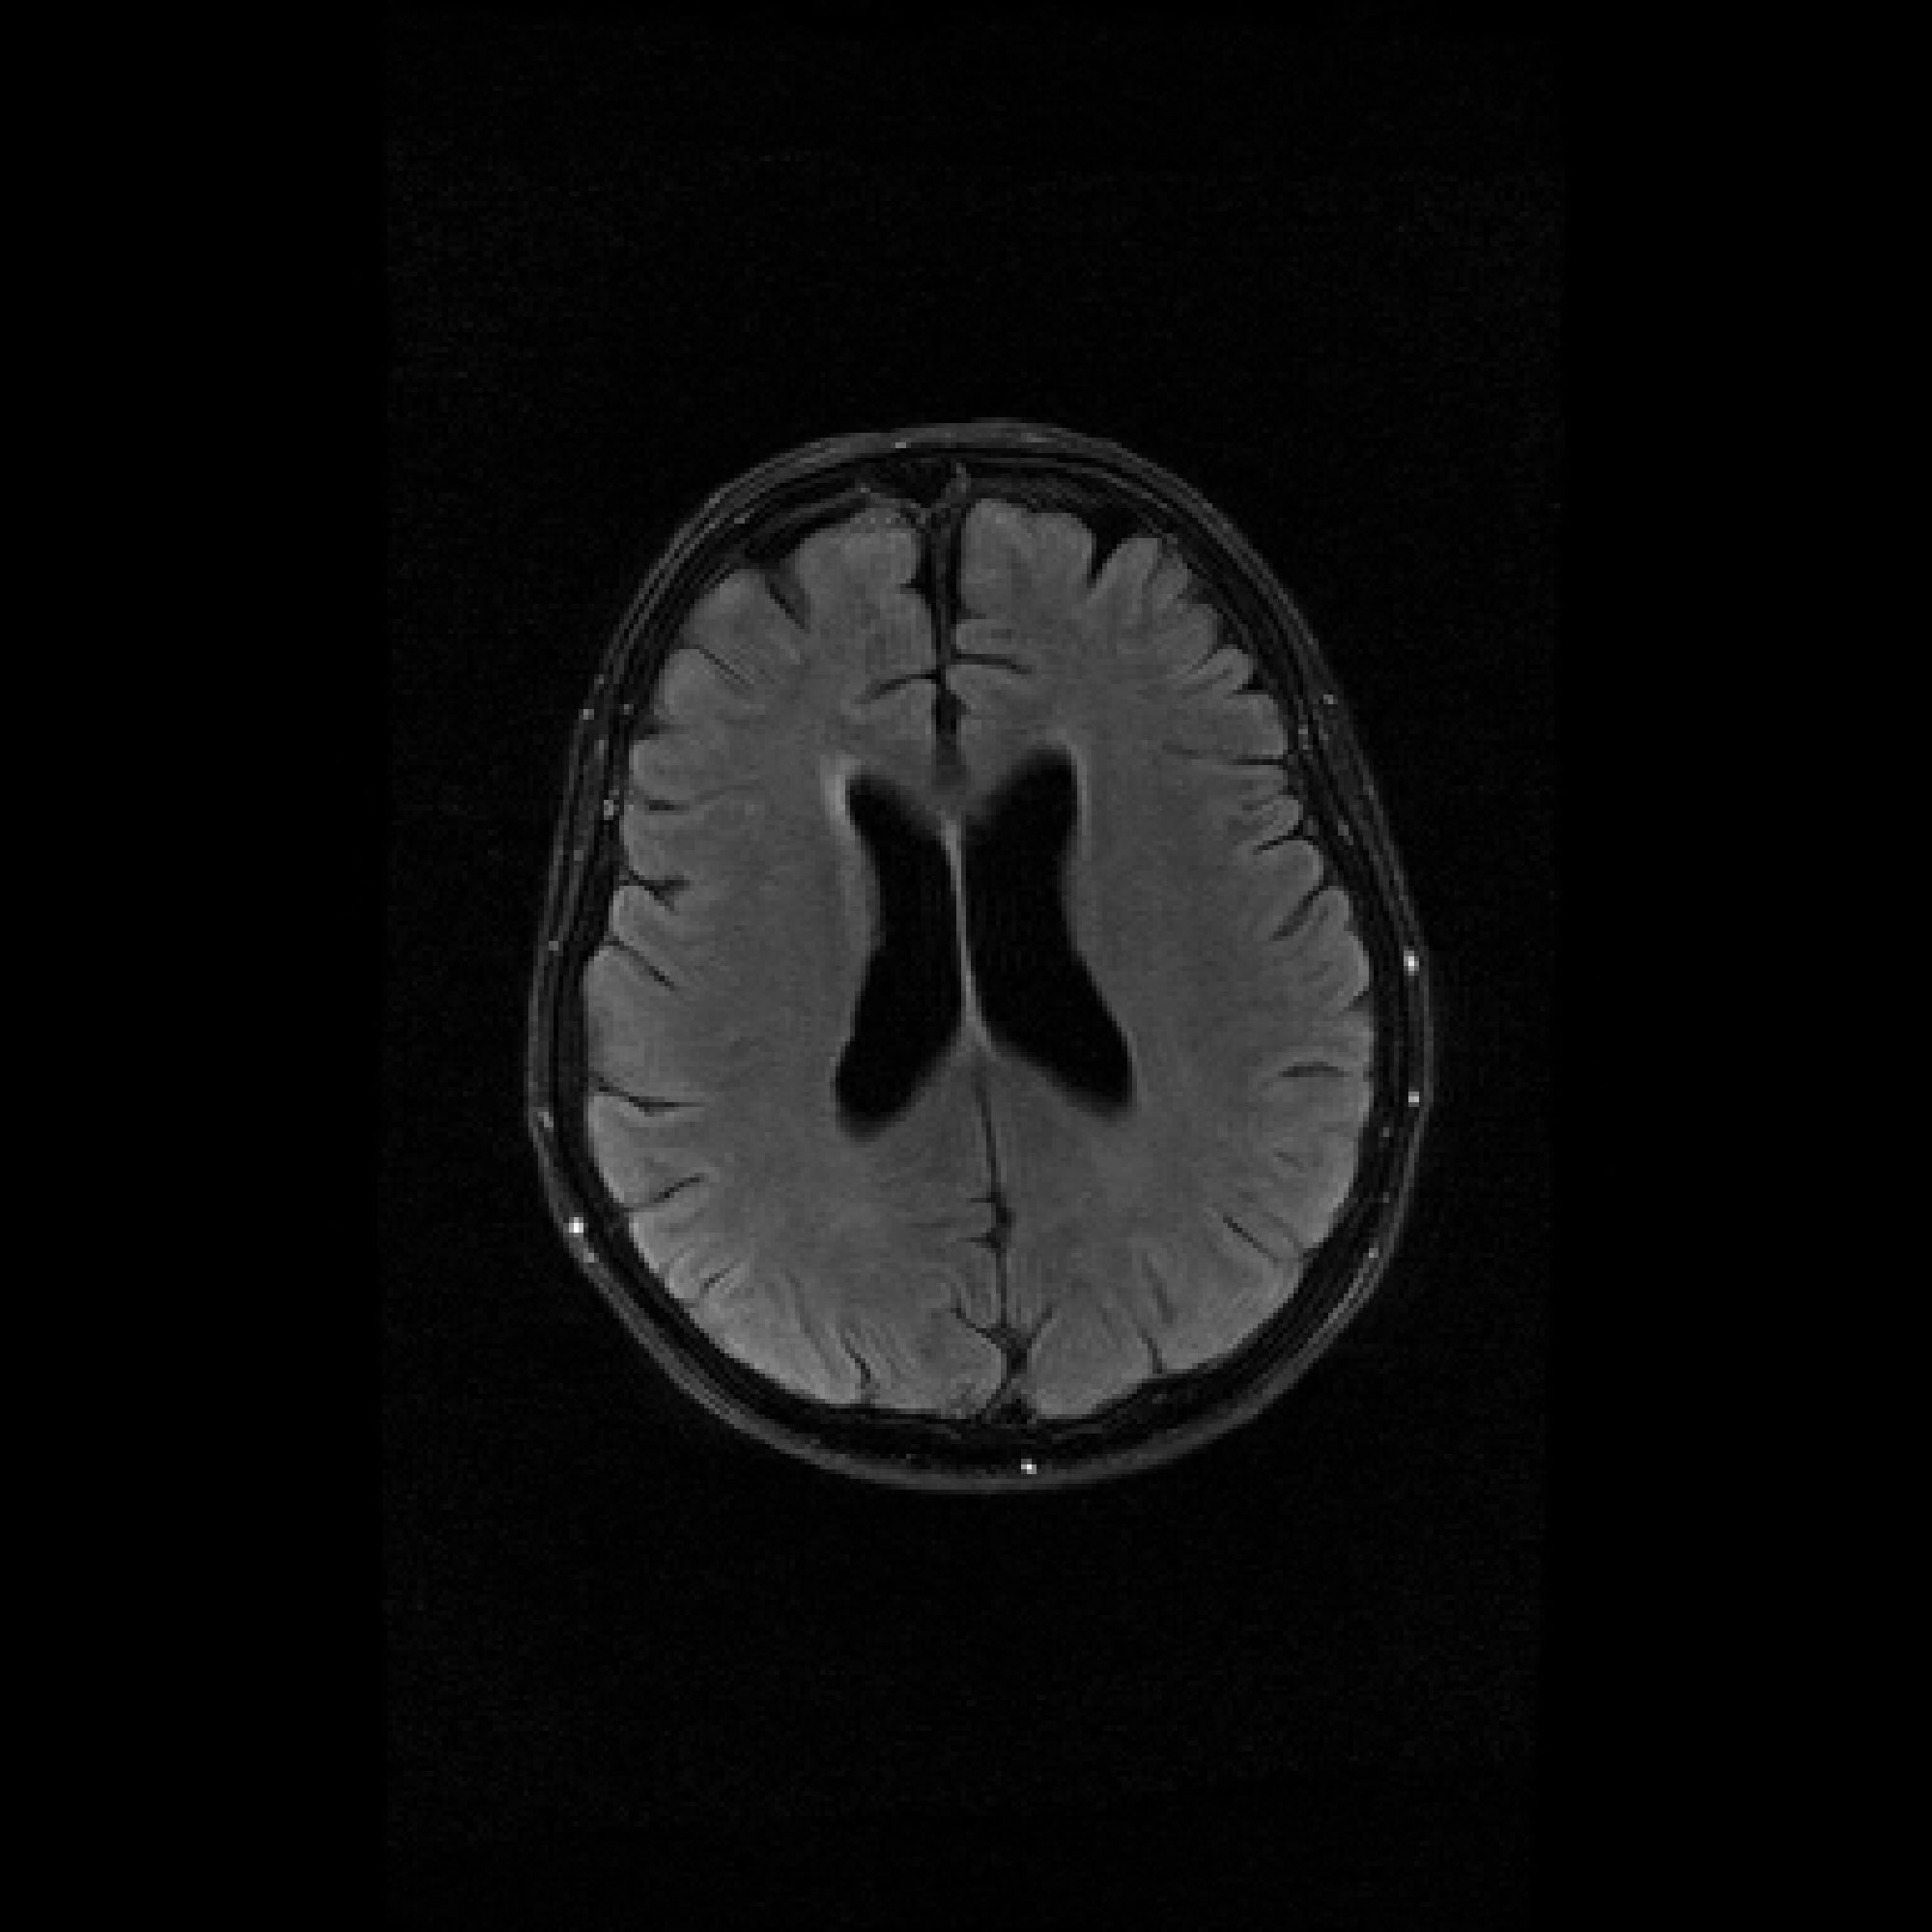

Figure 3: Pixel-wise standard deviations of reconstructions across 10 random k-space sampling masks (R=7R=7) of the same slice. Top to Bottom: models trained on 100, 500, and 1000 slices. PaDIS-MRI consistently exhibits lower pixel-wise variance (fewer bright regions) than FastMRI-EDM across training sizes and contrast types, indicating more stable reconstruction.

We assess reconstruction consistency by evaluating variability across 10 random k-space undersampling patterns (generated with different random seeds) for the same slice. Since the ground truth image is the same across undersampling masks, lower pixel-wise standard deviation indicates more stable reconstruction. We emphasize this is a consistency metric rather than calibrated posterior uncertainty. Such reliability is of particular interest to clinical settings where higher model consistency paired with superior accuracy can enhance medical decision-making.

Figure 3 visualizes these standard deviation maps, with brighter regions indicating higher variability between reconstructions. Across the 100-slice, 500-slice, and 1000-slice training regimes, PaDIS-MRI exhibits noticeably lower pixel-wise standard deviations compared to FastMRI-EDM, with the largest differences occurring at the smaller training dataset sizes. This suggests that decomposing the reconstruction problem into localized patches enables more stable learning of anatomical features, resulting in more reliable and consistent predictions from limited training data.

Table 1 quantifies these observations over our evaluation dataset. Due to computational costs of reconstructing each validation image across 10 random seeds, we randomly subsample a smaller evaluation set of 17 images (10 T2-axial, 5 T1-axial, 2 FLAIR) that preserves the contrast-type distribution of the training dataset. We crop each image to its original 384×320384\times 320 dimension to ignore deviations in our zero-padded regions, and report the pixel-wise standard deviation averaged across all test images. Again, PaDIS-MRI consistently achieves lower standard deviation values than FastMRI-EDM on average, with differences being most pronounced at smaller dataset sizes. These results further strengthen the case for patch-based diffusion priors in data-scarce settings. A breakdown of pixel-wise standard deviation averages by contrast type can be found in Appendix C.2.